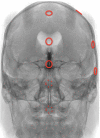

Background and Objectives Few simulation models are available that provide neurosurgical trainees with the challenge of distorted skull base anatomy despite increasing importance in the acquisition of safe microsurgical and endoscopic techniques. We have previously reported a unique training model for skull base neurosurgery where a polymer is injected into a cadaveric head where it solidifies to mimic a skull base tumor for resection. This model, however, required injection of the polymer under direct surgical vision via a complicated alternative approach to that being studied, prohibiting its uptake in many neurosurgical laboratories. Conclusion We report our updated skull base tumor model that is contrast-enhanced and may be easily and reliably injected under fluoroscopic guidance. We have identified a map of burr holes and injection corridors available to place tumor at various intracranial sites. Additionally, the updated tumor model allows for the creation of mass effect, and we detail the variation of polymer preparation to mimic different tumor properties. These advancements will increase the practicality of the tumor model and ideally influence neurosurgical standards of training.